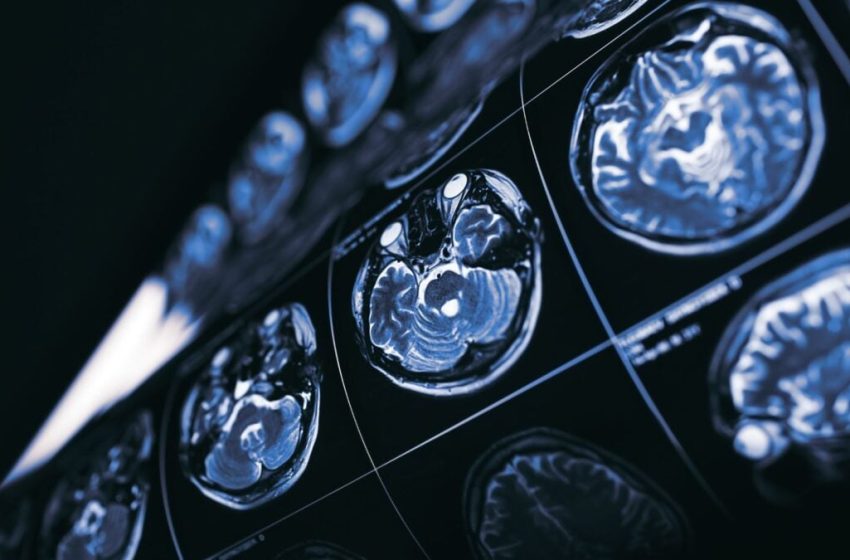

What If Cancer Holds the Key to New Treatments for Alzheimer’s Disease?

The enemy of our enemy could very well become our friend. Scientists have possibly uncovered a new approach to treating Alzheimer’s disease—one tied to the development of cancer.